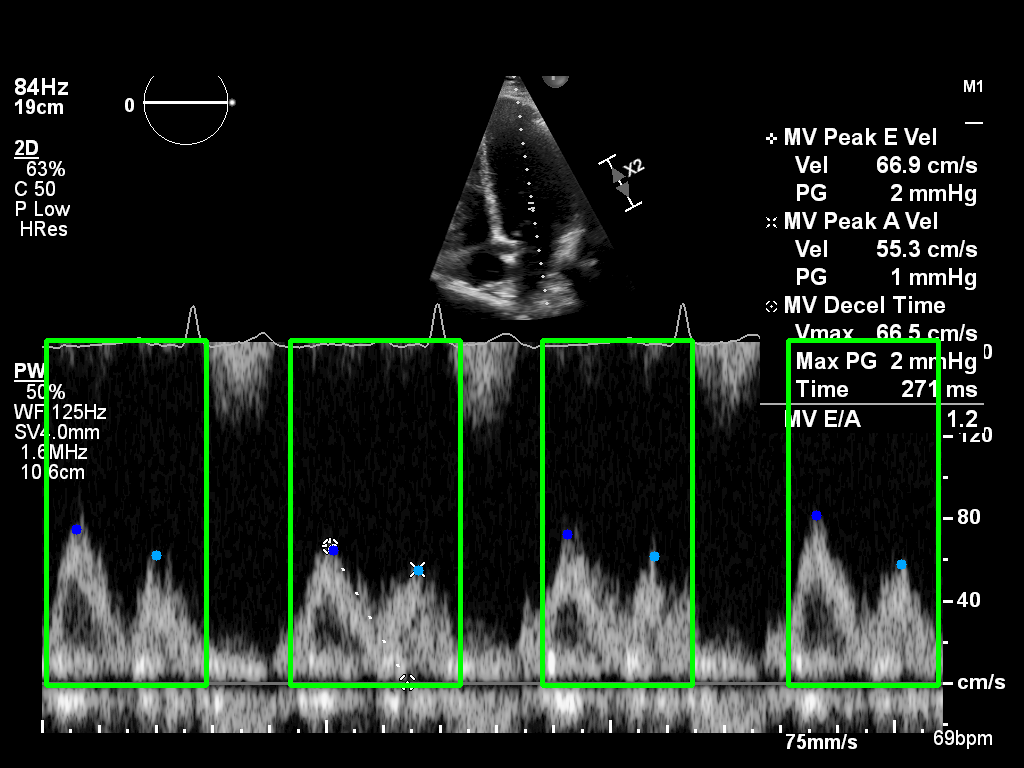

The Doppler velocity profile consists of two waves:

- E-wave — early ventricular filling

- A-wave — atrial contraction phase

Accurate measurement of these waves is critical for diagnosing diastolic dysfunction.

Expert cardiologists manually annotated E- and A-wave peaks, and DICOM-formatted Doppler images were zero-padded to 1024×1024 px.